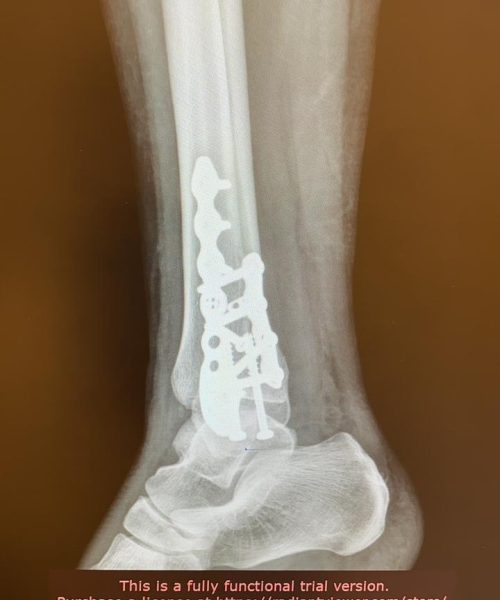

Fraturas no pé e tornozelo referem-se à quebra dos ossos nessas regiões, podendo ocorrer devido a traumas, quedas ou impactos.

Os tratamentos são indicados para pacientes com fraturas que podem variar de simples a complexas, comprometendo a função e a estabilidade.

O tratamento pode incluir imobilização com gesso, tala ou até mesmo cirurgia, dependendo da gravidade da fratura. A cirurgia pode envolver o uso de pinos, placas ou parafusos para fixar os ossos.

Riscos cirúrgicos incluem infecção, má cicatrização óssea e a necessidade de remoção posterior de hardware. O cirurgião deve discutir esses riscos detalhadamente com o paciente.

A recuperação pode variar significativamente, dependendo da gravidade da fratura e do tipo de tratamento. Geralmente, envolve um período de imobilização seguido por fisioterapia para restaurar a função e a mobilidade.